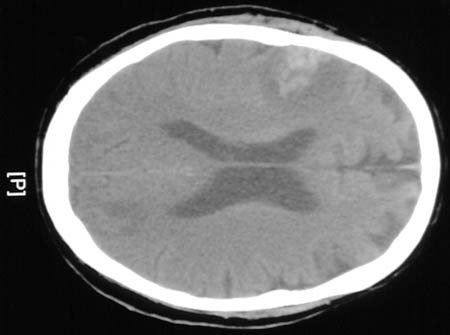

![]() | In this CT scan can be seen a lesion with central enhancement from hemorrhage and surrounding edema. This proved to be one of several foci of amebic encephalitis due to Acanthameba infection in a bone marrow transplant patient. CNS infection by free-living ameba, including Acanthameba and Naegleria, is rare but life-threatening. |